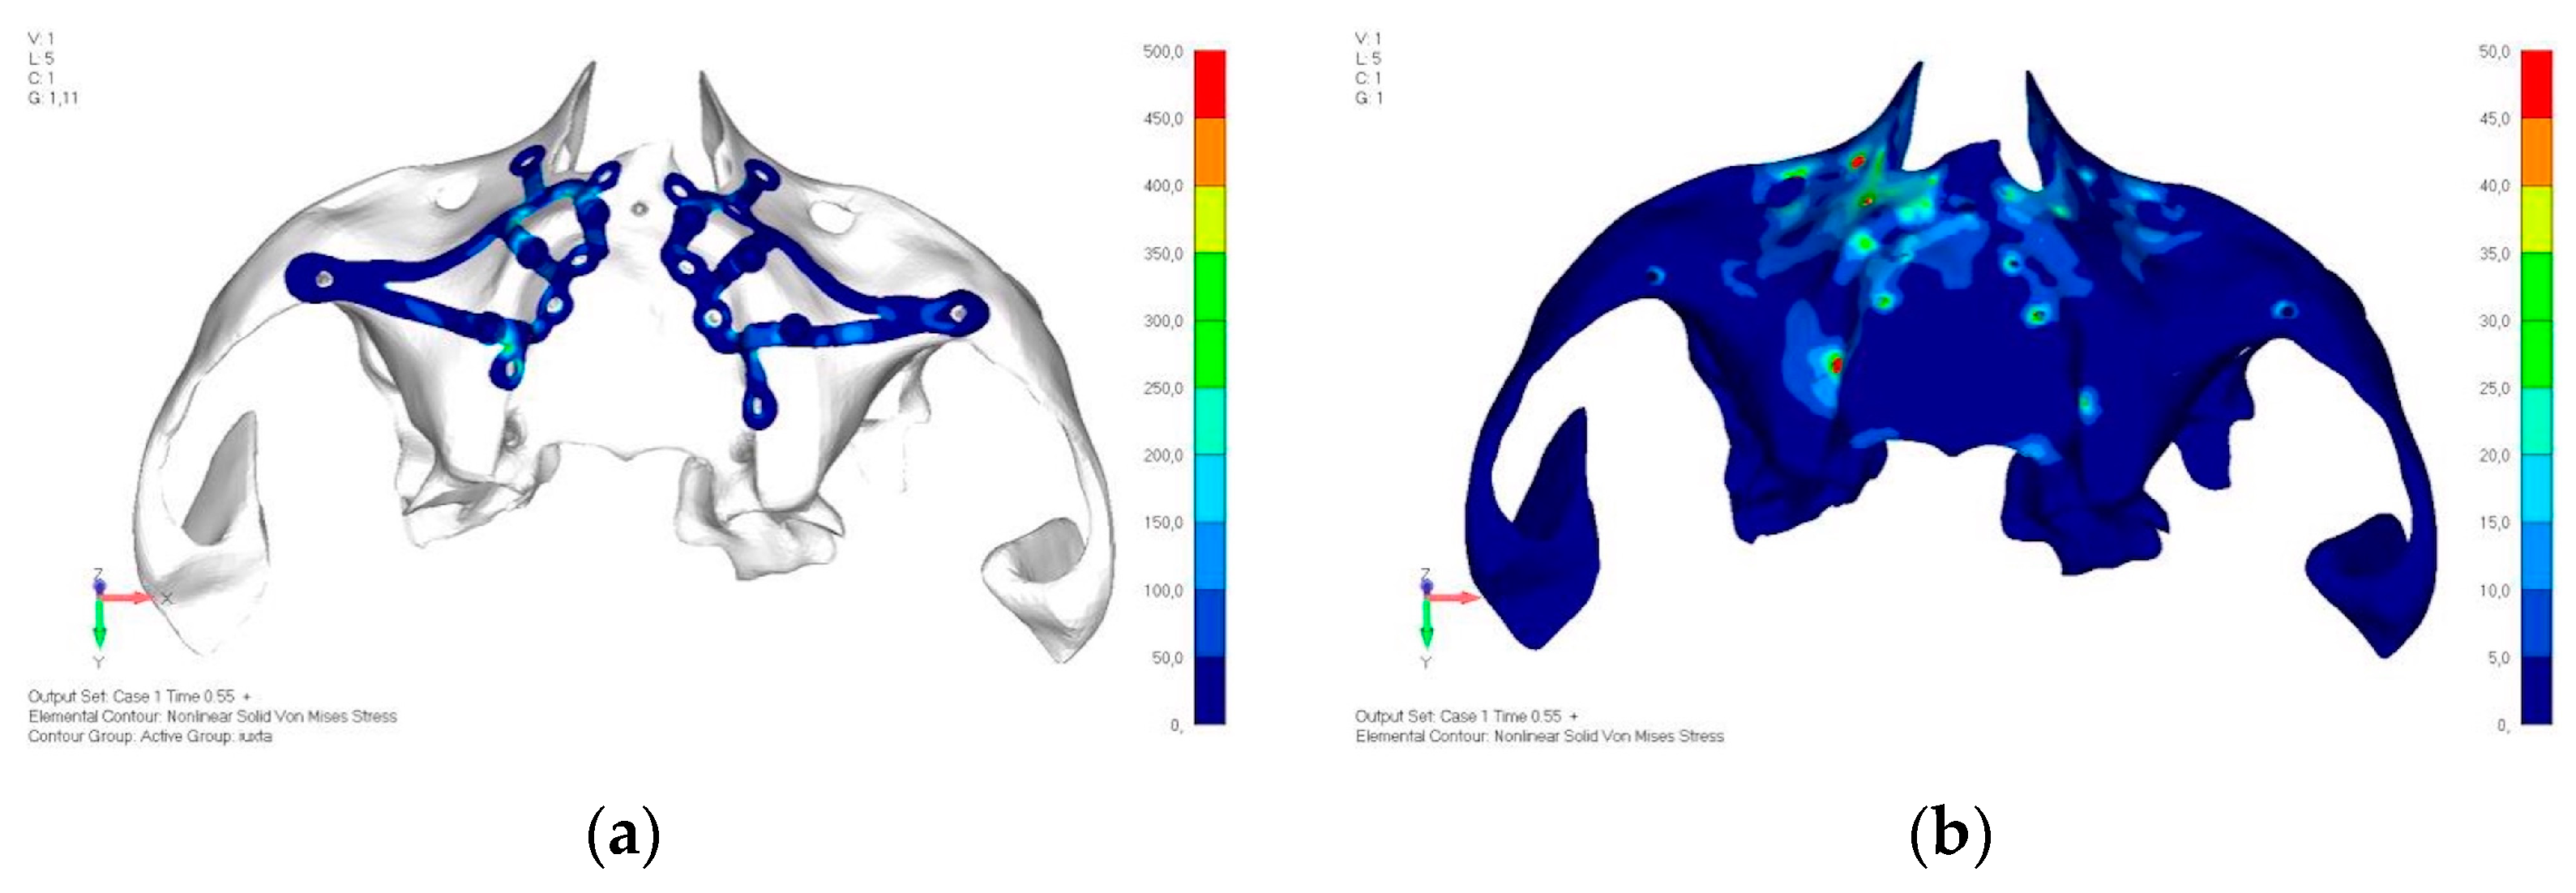

- Model V4. The previously added screw was relocated towards the frontal process, aligning it vertically with the other screws and ensuring that both arms of the first and second abutments connect to this screw (Figure 14). This solution proved to be more effective than V3; the addition of the screw reduces the stress on the other screws and on the support. The area where stress exceeds 50 MPa in the vicinity of the screws is now more contained, and the crestal support shows stresses between 30 and 35 MPa, which are absolutely acceptable (Figure 15a,b).